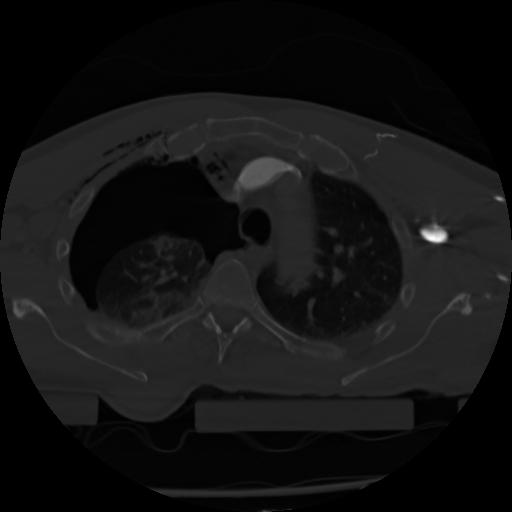

21 ANGIO,CE,Axial,3.0,ANGIO,,